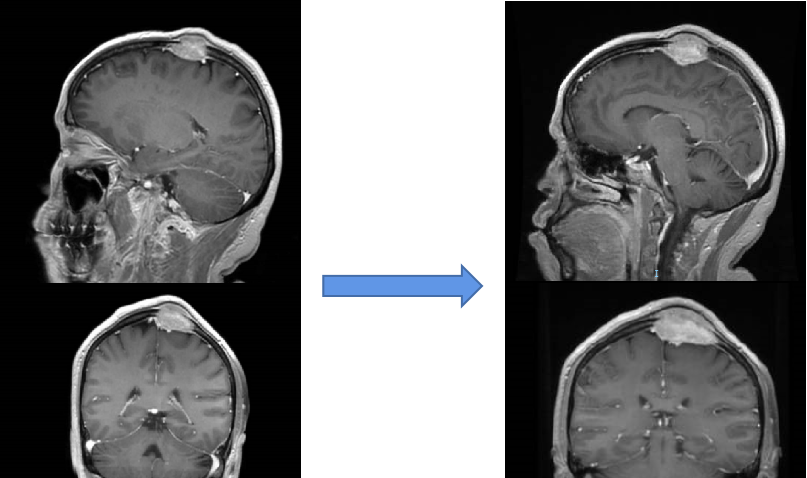

图2A

图2B